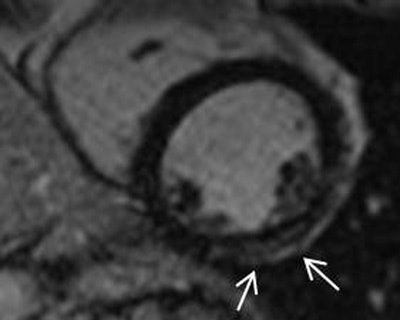

Above and below: Short-axis MR images from a 1.5-tesla scanner showing late gadolinium enhancement in two different female Duchenne muscular dystrophy carriers (38-year-old carrier above, 34-year-old carrier below). All images courtesy of Dr. Juliane Schelhorn.Cardiac pathologies occur frequently in Duchene carriers, and because of this, regular risk assessment seems advisable in these individuals, she concluded. The frequency would have to be sorted out depending on the carrier.

The results showed abnormalities in all 15 patients, including decreased LV end-diastolic volumes, and increased LV end-systolic volumes. There were also decreased ejection fraction measurements. Late gadolinium enhancement, mainly midmyocardial inferolateral, was found in 60% of the patients, Schelhorn said.

There was LV noncompaction in 13% of carriers (apically accented), and regional hypokinesia in 47%. There was regional myocardial thinning (more than one segment) in 80% of patients. Finally, late gadolinium enhancement was seen in 60% of patients.